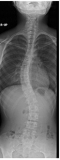

放射線科では、放射線技師が24時間体制で業務に取り組んでいます。

患者さまが心から安心して気持ちよく検査を受けていただけるよう、スタッフ一人一人が「思いやり」の精神を持って接するよう心がけております。

検査機器の紹介